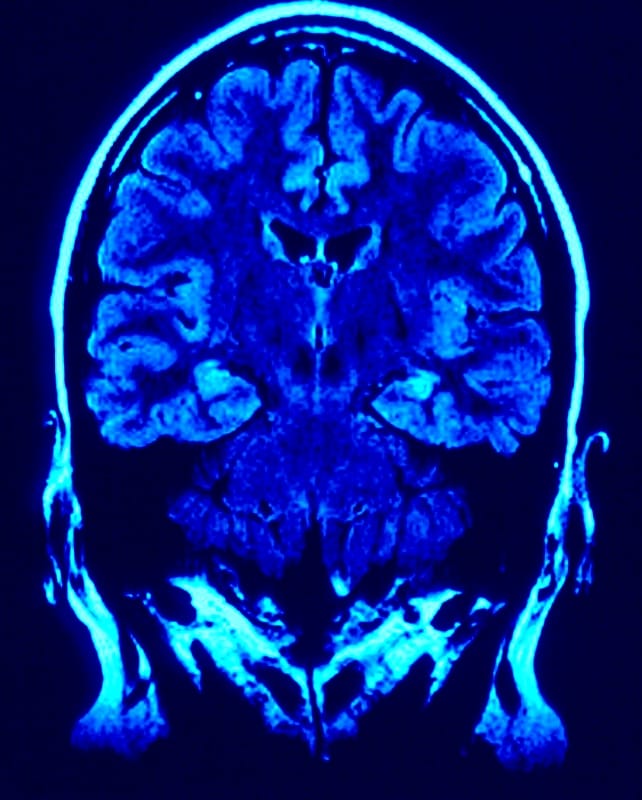

Neuroscience and Buddhism converging on the inconstant self

An increasing number of scientific researchers are referencing and drawing on Buddhism in their studies, especially in the field of neuroscience.